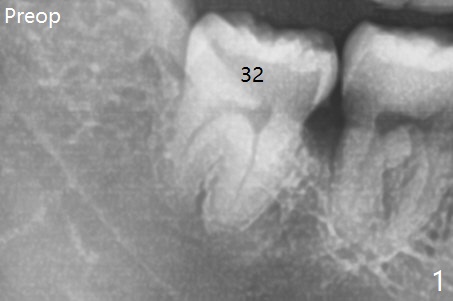

A 40-year-old man requests extraction of the teeth #17 and 32 (Fig.1).